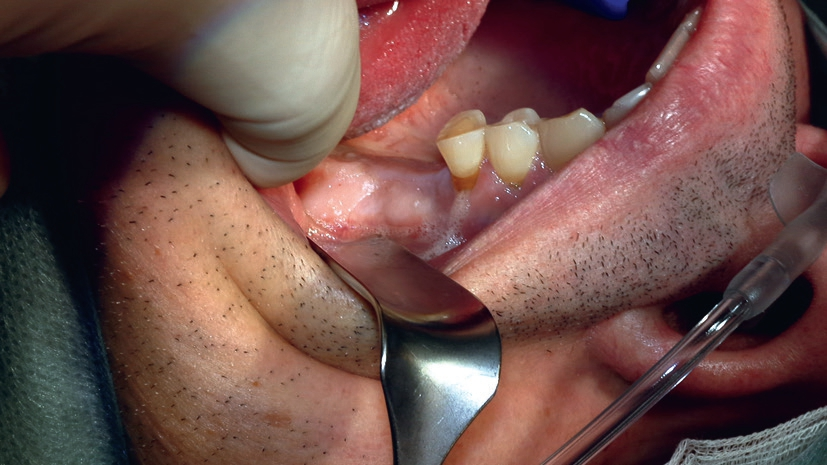

Der Patient stellte sich in unserer Praxis mit Zahnverlust in regio 26 und 27 vor. Trotz extrem dünnem Kieferknochen war eine Versorgung mit Implantaten gewünscht (Abb. 1). Nach konventionellen Standards wäre in diesem Fall ein zweiteiliger externer Sinuslift durchzuführen, bei dem zunächst der Kieferknochen freigelegt und mit körpereigenem und/oder fremdem Knochenersatzmaterial aufgefüllt wird, um nach einer mehrmonatigen Einheilzeit mit der Implantation zu beginnen.

Im vorliegenden Fall kamen die Piezochirurgie und die Bestimmung des Resonanz-Frequenz-Analyse-Wertes (RFA) zum Einsatz, um Knochenaufbau und Implantation in nur einer Sitzung durchzuführen, ohne die Stabilität des Zahnersatzes zu gefährden (Abb. 2).